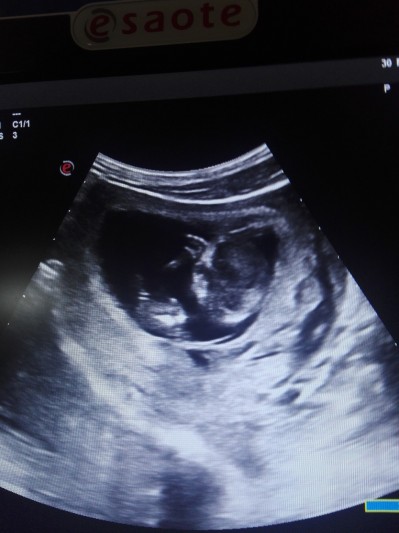

Bebek varmı resimli guzel anneler ben anlamıyorum da 6haftalık

Gebelik haftası 6haftalık

Keseyi gösterdi mi size

Evt kese ıkı tane gordum bebek yok dendi bebde merak ettim acaba yanlıs mı soyledı bebek varmı yok mu diye anlamadım

İki minik kese var gözünüz aydın 10 gün sonra görünür bebekler

Nerden anladınız herjez kese yok diyor ama doktor iki kese oldugunu soylefı bnde goremedım de

Benim de kesem ilk küçüktü yakınlaştırınca gördüm sol üstte ordan anladım canm

canım kesr nerde hiç anlayamadım çok değişik kese olduğu zaöan siyah boşluk oluyor burda en solda orta kısımda var ama o kese olsa neden o tarafı çekmesin anlam veremedim kese ölçüsüde yok normalde dr alıyor ölçüsünü kayıt ediyor